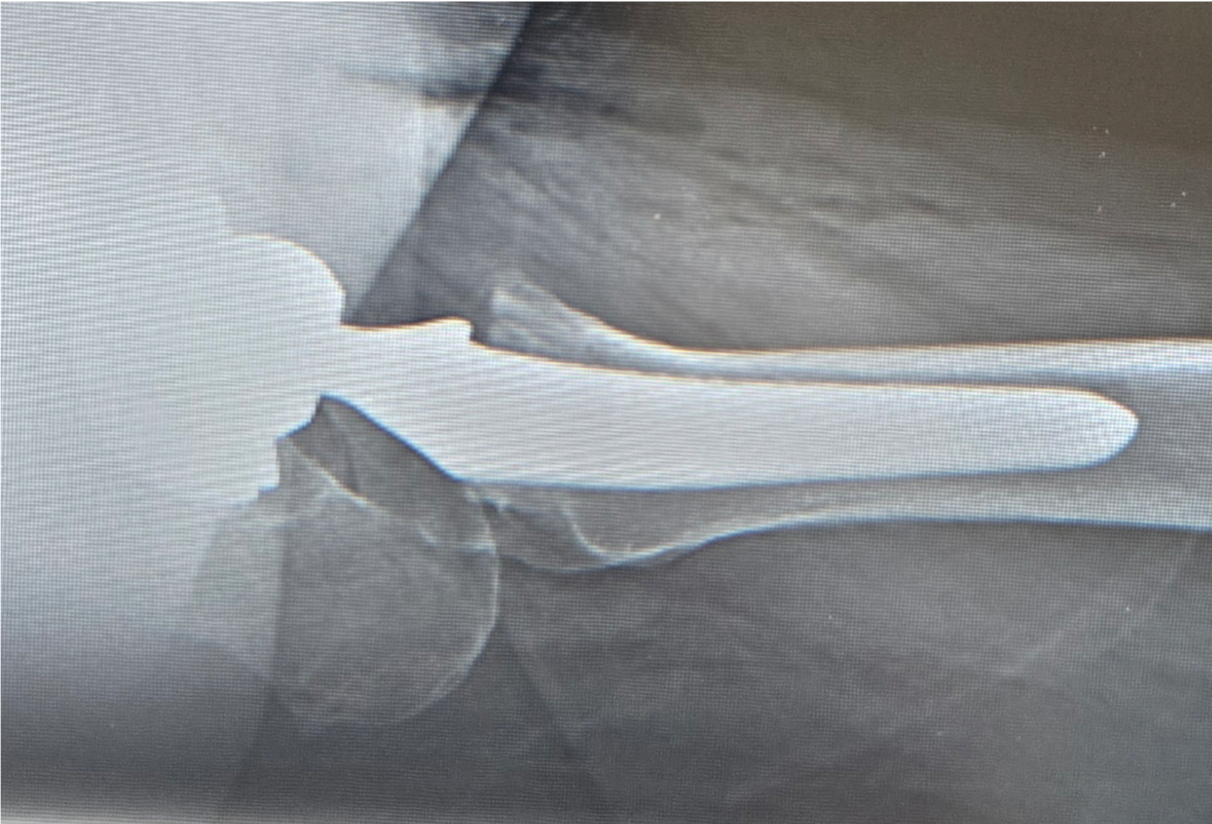

そのためにはインプラントの正確な設置も非常に重要となります。 股関節のカップの設置の理想は、正面から見て、外側に40度、側面から見て、前側に15度の角度がついているものが脱臼リスクの最も少ない理想の設置と言われています。